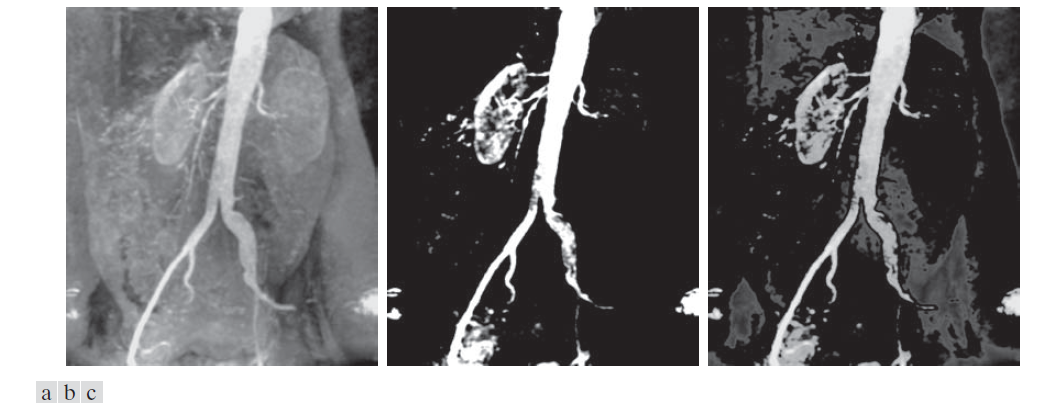

图 3.12(a) 是肾脏区域附近的主动脉血管造影图(有关此图像的详细信息,请参见 1.3 节)。本例的目的是使用强度级分片来增强由于注射造影剂而显得比背景更亮的主要血管。图 3.12(b) 显示了对图 3.11(a) 中的图像进行变换的结果。所选波段位于强度等级的顶部附近,因为感兴趣的范围比背景更亮。这种变换的最终结果是,血管和肾脏部分呈现白色,而所有其他强度区域呈现黑色。这种增强类型会生成二值图像,可用于研究造影剂流动的形状特征(例如,检测阻塞情况)。

如果我们关注的是感兴趣区域的实际强度值,可以使用图 3.11(b) 所示形式的变换。图 3.12(c) 展示了使用这种变换的结果,其中,平均强度周围的中灰色区域中的一段强度被设置为黑色,而所有其他强度保持不变。由此可见,主要血管和部分肾脏区域的灰度色调保持不变。当我们关注的是测量图像序列中造影剂的实际流量随时间的变化时,这样的结果可能很有用。

---------------------------------图 3.12:(a)主动脉血管造影图。(b) 使用图 3.11(a) 所示分片变换的结果,其中感兴趣的强度范围选择在灰阶的上端。(c)使用图 3.11(b) 所示变换的结果,其中选定的范围设置为接近黑色,以便保留血管和肾脏区域的灰色。(原图由密歇根大学医学院的 Thomas R. Gest 博士提供。)--------------------